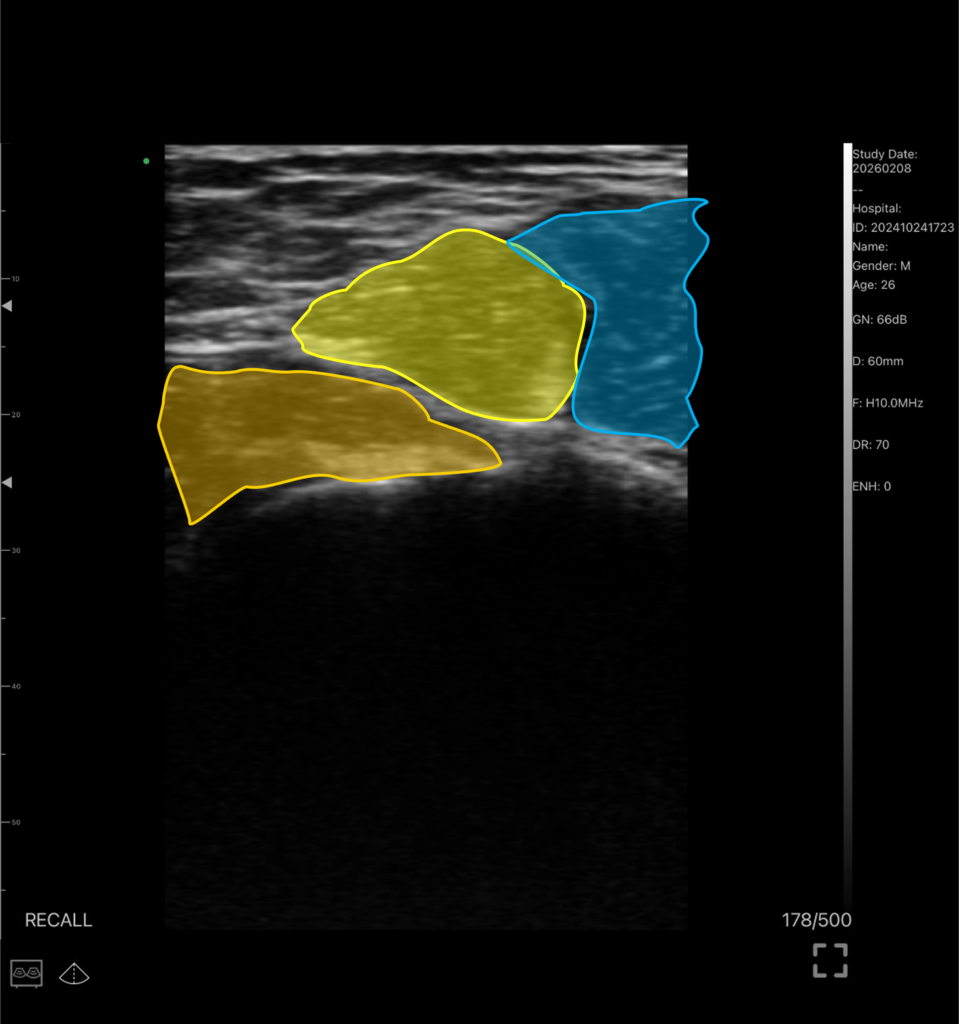

拘縮期では痛みの出ない範囲で少しずつ動かしていきます。エコーで確認しながら癒着の強そうなところに鍼治療を行い、筋肉を収縮させながら徐々に可動域を出していきます

*黄色が上腕三頭筋、オレンジが小円筋、青が大円筋

可動域制限の原因になりやすい部位となります